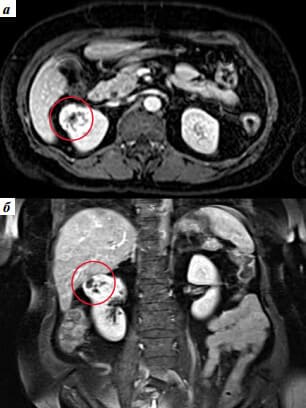

- Разбира се. Първият случай е свързан с камъни в бъбреците. С мен се свърза 27-годишен мъж с болка в дясната страна която започва от гърдите и завършва някъде в областта на пикочния мехур. Болката се проявяваше с кратки спазми, конвулсии, студена пот и се появяваше на вълни. Изображението показва наличието на 19 мм камък, заседнал в горната част на бъбрека. Предписахме Nefro Aktiv . за разбиване на камъни в бъбреците. В рамките на два дни от използването му камъкът започна да се чупи и излезе напълно за една седмица. Пациентът не чувства дискомфорт.